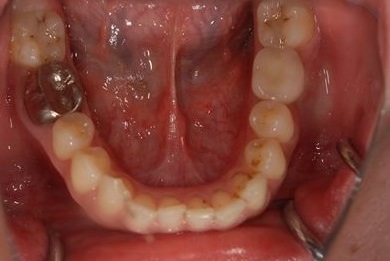

| 性別/年齢 | 女性 / 30歳 | ||||||||||||||||||||||||||||||||

| 主訴 | 銀歯がはずれた奥歯にひびが入っており、抜歯しなければいけないため、インプラントの治療相談を希望。 | ||||||||||||||||||||||||||||||||

| 治療内容 | インプラント1本、メタルボンドセラミック1本 | ||||||||||||||||||||||||||||||||

| 総治療費 | 401,363円 | ||||||||||||||||||||||||||||||||

| 治療期間 | 5ヶ月 |